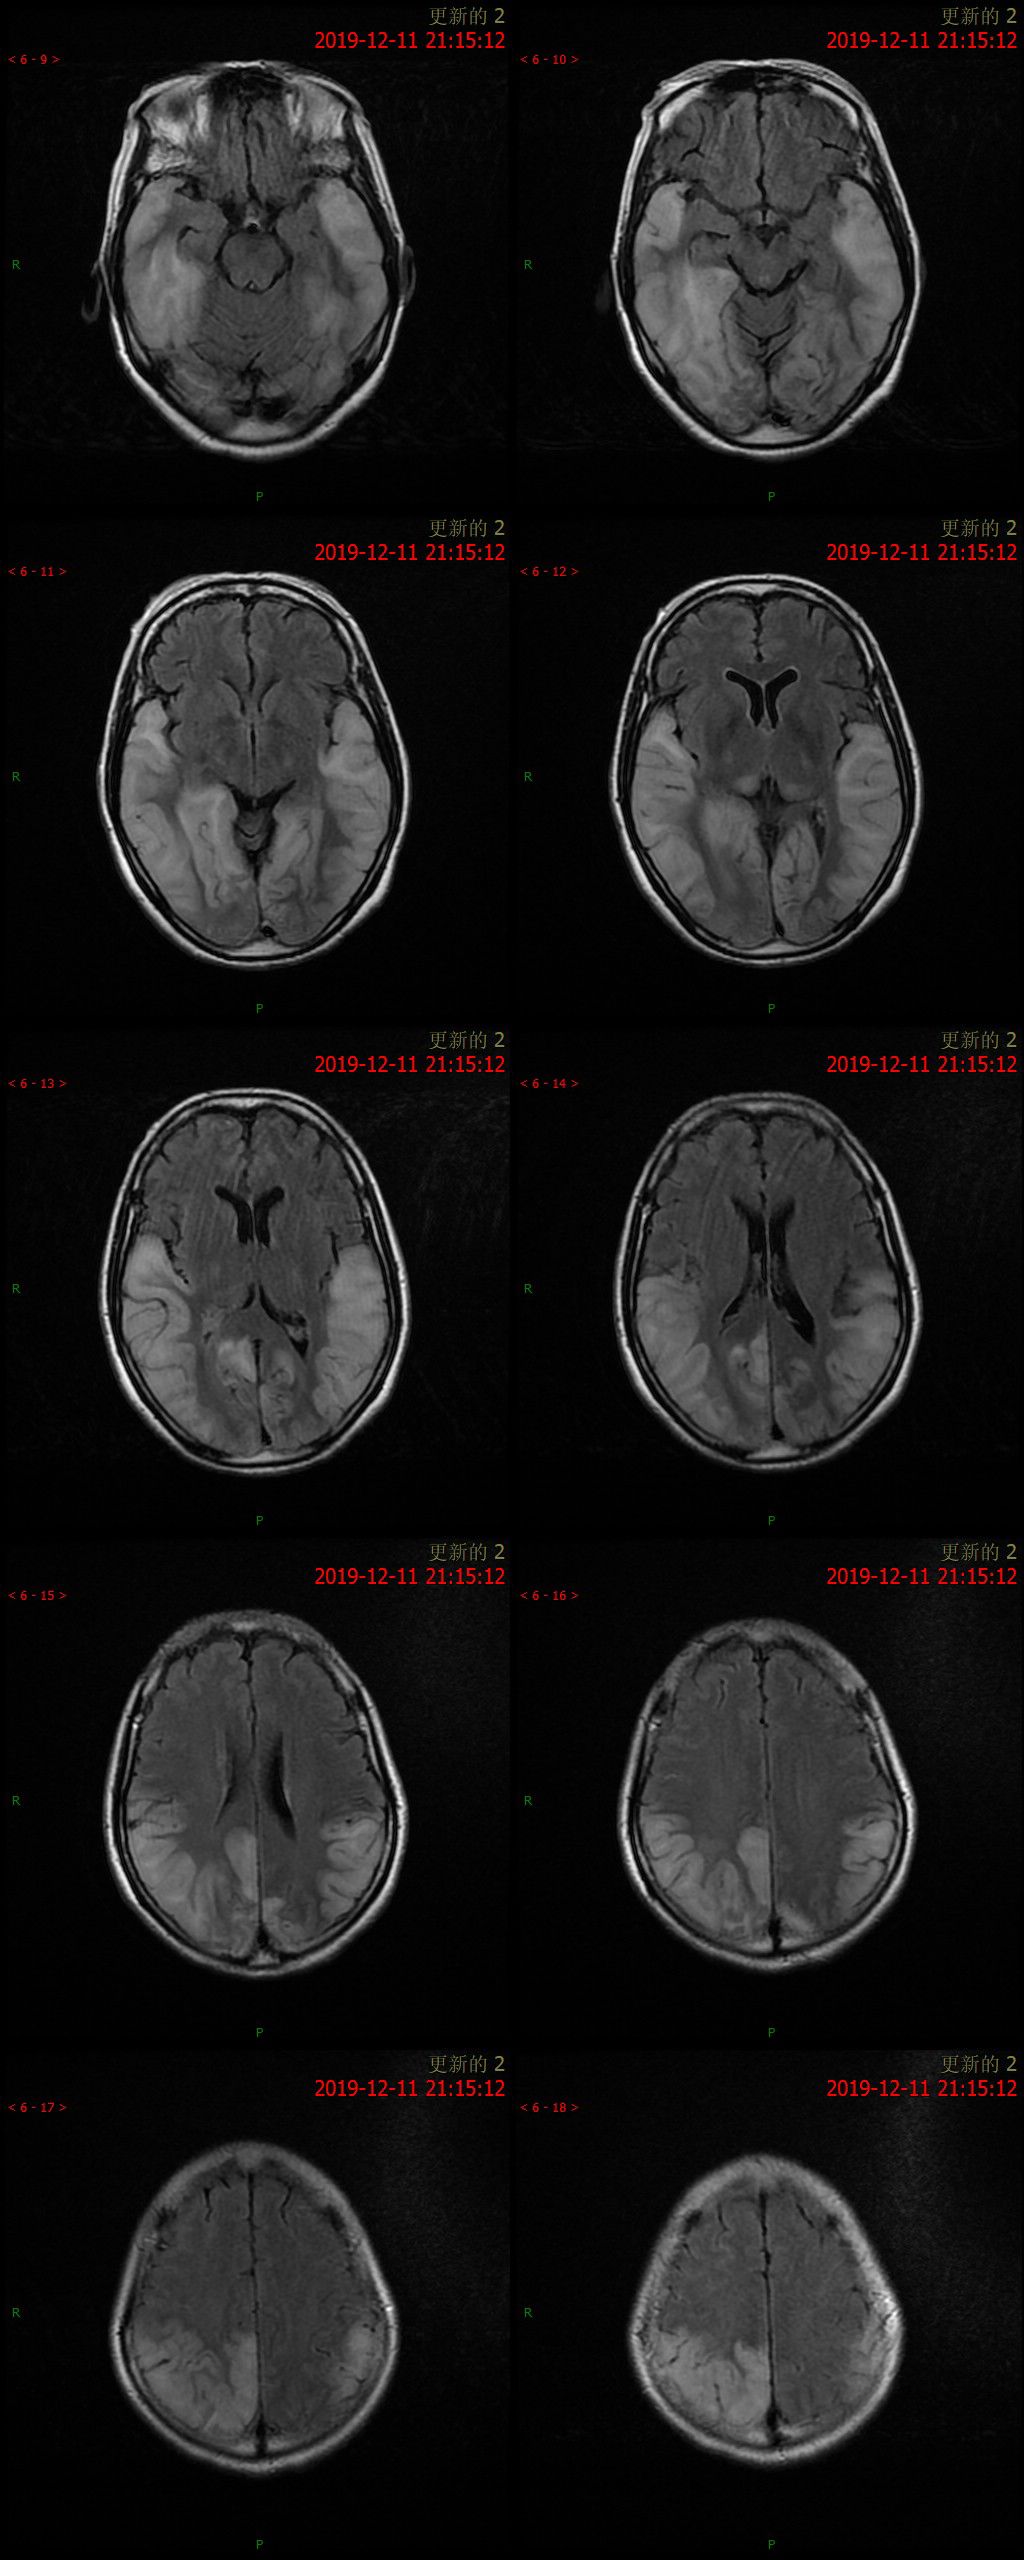

12.11 日 MR 平扫

患者为中年女性,临床症状不重,影像表现明显。双侧大脑半球多发病变,DWI 呈高信号,呈非对称性分布,且病灶分布呈跨血管支配区分布,DSA 为正常表现,可以排除脑梗死。短期内病灶迅速进展,MRS 可以看到明显倒置的乳酸双峰,考虑 MELAS。

①以大脑皮质灰质损害为主, 多累及半球后部颞顶枕叶,其次为颞叶、海马和海马旁回、额叶、小脑等,呈游走性、多变性、此起彼伏等表现;其特点是不按解剖血管分布, 累及皮质和皮质下白质, 可见皮质的层状异常信号;

②对称性双侧基底节、丘脑, 脑干等灰质核团损伤的异常信号;由于灰质核团的细胞代谢活动比白质纤维强, 容易受累;

③灰质和白质散在的异常信号;白质病变多侵犯较新的周围白质, 即皮质下和三角区后部白质。